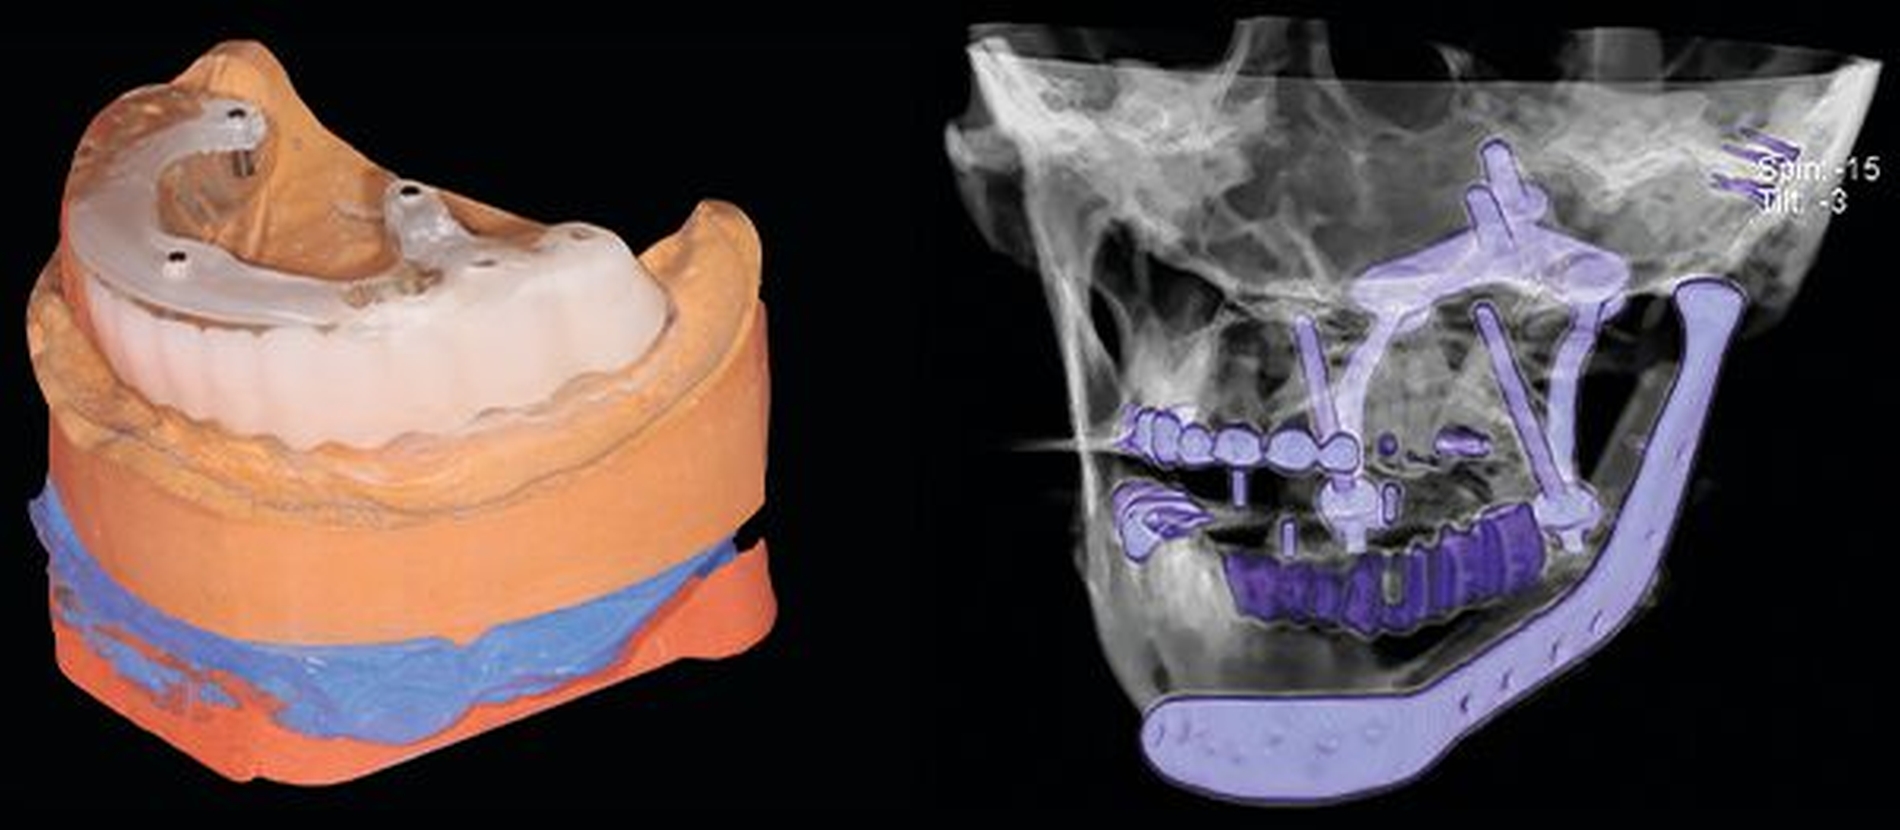

Abbildung 2 zeigt in der CT die Ausgangssituation mit frakturierter Rekonstruktionsplatte und massiver Okklusionsstörung durch die Innenrotation der Mandibula.

Die CT-Daten wurde in die Software der Firma 3D Systems (3D Systems, Littleton, USA) eingelesen und aufbereitet. Dadurch ist es möglich, relevante Areale zu segmentieren und bei der Planung virtuell frei zu positionieren. Dies kann in Abbildung 3 gut nachverfolgt werden. Die rotierte Mandibula wurde in ihre ursprüngliche Position und somit die Restbezahnung in Okklusion mit dem Oberkiefer gebracht.

Die neue Okklusion wird postoperativ mittels intermaxillärem Splint gesichert (Abbildung 4). In den Folgeschritten werden die Resektionsgrenzen festgelegt und die notwendigen Fibulasegmente angepasst (Abbildung 5).

Die alloplastische Fossakomponente wird in der ehemaligen Fossa articularis platziert und am Arcus zygomaticus mit Schrauben fixiert. Bei dem BIOMET System wird der Rotationspunkt auf der Translationsbahn des natürlichen Kondylus nach kaudal gelegt, um die natürlichen translatorischen Bewegungen zu imitieren und die interinzisale Öffnung zu vergrößern [van Loon et al., 1999; van Loon et al., 2000]. In dem Plattendesign ist der Kondylus integriert, so dass hier keine Schwachstelle durch Schraubverbindungen entsteht (Abbildung 6).

Die zur Konstruktion der TEP konstruierten Teile, wie das PSI, die Fossa und Schablonen wurden durch Firma Biomet Microfix Inc. (Jacksonville, Florida, USA; [Vertrieb: Zimmer Biomet Deutschland GmbH]) hergestellt. Die Platte besteht aus einer Titan-Aluminium-Vanadium-Legierung, der Fossaanteil aus ultrahochmolekularem Polyethylen (UHMWE-PE) (Abbildung 7).

In Abbildung 8 sind die notwendigen Resektions- und Bohrschablonen dargestellt, die intraoperativ die Schnittgrenzen und Bohrlöcher festlegen.